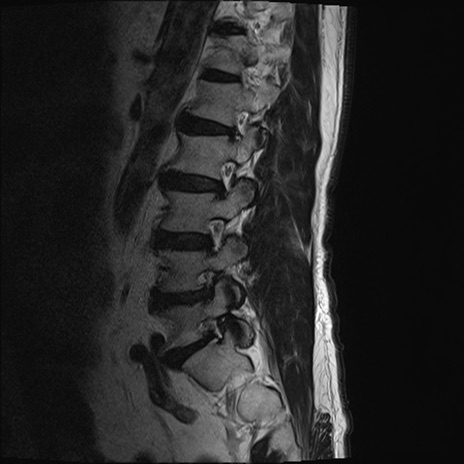

【整形】TIPS症例2 腰椎MRI T2WI(矢状断像)

【症例】70歳代男性

【主訴】左下肢痛

【現病歴】2週間前くらいから腰痛、左下肢痛あり。左臀部から大腿、下腿外側のしびれが常時ある。歩行とともに同部位の痛みあり。

【身体所見】Lasegue70-/60+、Bragard-/±、PTR ±/±、ATR -/-、IP 5/5、TA 5/4、TS 5/5、EHL 右第1足趾なし/3、FHL 5/5、hypersthesia(-)、足背動脈触知良好

異常所見と診断は?